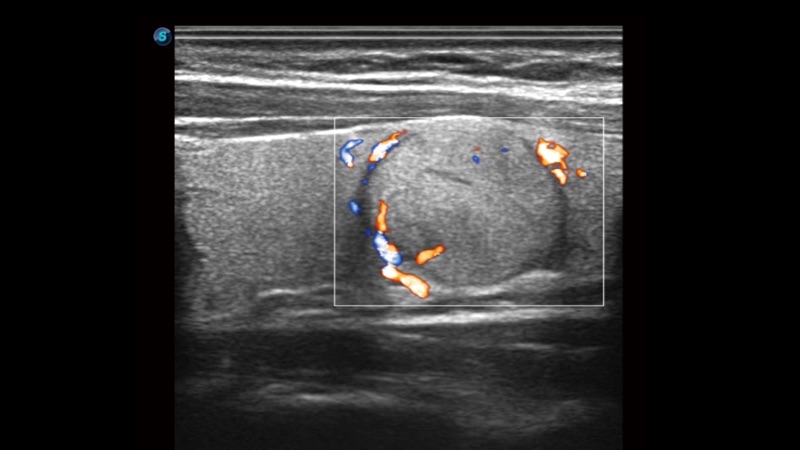

腔内探头

凭借狗万官方网站先进的成像技术和优异的探头技术提供的清晰的图像表现,您可以更自信地做出临床决策。